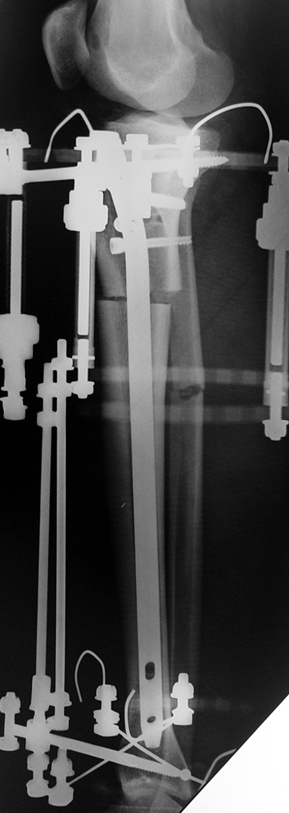

İntramedüller çivinin yerleştirilmesi ve osteotomi: Hasta traksiyon masasına supin pozisyonda yatırılır ve sağlam bacak altta olacak şekilde bacaklar makas pozisyonuna alınır. Standart yolla piriformis çukurundan medulla içine girilir ve kılavuz tel üzerinden kullanılacak çividen 1.5 mm daha kalın oyucu ile medulla oyulur. Proksimal femur, çivinin proksimali daha kalın olduğu için daha kalın oyulur. Radyografide osteotomi hattı planlaması yapılır. Planlama yapılırken uzatma sonunda distalde en az 8 cm. çivi kalması stabilizasyon için gereklidir. Kortikotomi perkütan olarak kortikotom ile tamamlanır. Daha sonra kılavuz tel çivinin boyunu ölçmek için distale ilerletilir. Uygun boyda intramedüller çivi çakılır. Son olarak çivi proksimalden kilitlenir ve bir adet dren konarak ameliyatın birinci kısmı tamamlanır.

Eksternal fiksatör uygulanımı: İntramedüller çiviye değmeden aşağıya ve yukarıya üçer adet Schanz vidası gönderilir. Vidalarla çivi arasında en az 1 mm den fazla mesafe olmalıdır.

Postoperatif Bakım: Distraksiyona (Kemik parçalarının arasının birbirinden uzaklaştırılması yöntemi) 10. günde başlanır. Günde 4 defa 6 saatte bir 0.25mm uzatma yapılır. Operasyondan 1-2 gün sonra kalça ve diz çevresi hareketlere başlanır. Alt ekstremite kısalıklarının tedavisi uzun yıllar boyunca hem hasta hem de cerrah için zorluklarla dolu olmuştur. İlizarov’un distraksiyon osteogenezisi kavramını tanımlamasından sonra geliştirilen teknikler bu konuda yeni bir çağın öncüleri olmuşlar ve daha önceki yıllarda görülen komplikasyonların oldukça azaldığı uygulamalar olarak anılmışlardır.

Biz son zamanlarda, seçilmiş vakalarda, uzatma sonrası uzunluğu ve “alignment’ı” korumak amacı ile unilateral dinamik aksiyel fiksatör ve kilitli intramedüller çivi kombinasyonunu tercih etmekteyiz. Bu yöntemin ön şartları medullanın en dar çapının 7 mm.’den geniş olması ve uzatma sonrası distalde en az 8 cm. uzunluğunda çivi kalabilmesidir. İntramedüller çivi hem uzatma esnasında femurun üzerine gelen makaslama ve bükülme kuvvetlerini nötralize etmekte hem eksternal fiksasyon süresini kısaltmakta, hem de yeni oluşan kemiği kırıklara karşı korumaktadır. Serimizde bir vakada subtrokanterik femoral osteotomi yapılmıştır. İntramedüller çiviye rağmen varus angulasyonu oluşması yönünde bir dezavantaj tespit etmedik.

İlizarov, distraksiyon osteogenezisi için endosteal kan dolaşımının önemini vurgulamıştır. Biz tüm vakalarımızda femuru oyarak intramedüller çiviyi çaktık; buna rağmen hiçbir vakada kallus oluşma süresi tahminimizden daha uzun olmadı. Bu yüzden medüller dolaşımın bozulmasına bağlı yeni kemik oluşma hızında bir yavaşlama olmadığını düşünüyoruz. Oyma sonrası meydana gelen revaskülarizasyon, intramedüller çivili fiksasyon stabilitesi ve erken fonksiyonel yüklenme bu gerçeğin temelini oluşturmaktadır. Eksternal ve internal fiksasyon yöntemlerinin kombine kullanımının potansiyel dezavantajları kan kaybının artması, intramedüller infeksiyon, yağ embolisi olasılığı ve aşırı metal yüküdür. Bunların içinde en çok korkulan problem bir çivi dibi infeksiyonun tetikleyeceği derin intramedüller infeksiyondur (panosteomyelit). Bizim serimizde bu yönde hiçbir komplikasyon gelişmemiştir. Bu olası komplikasyonun önlenmesi amacı ile uzatma sonundaki kilitleme medialden yapılmalıdır; ayrıca intramedüller çivi ve eksternal fiksasyon pinlerinin teması önlenmelidir.